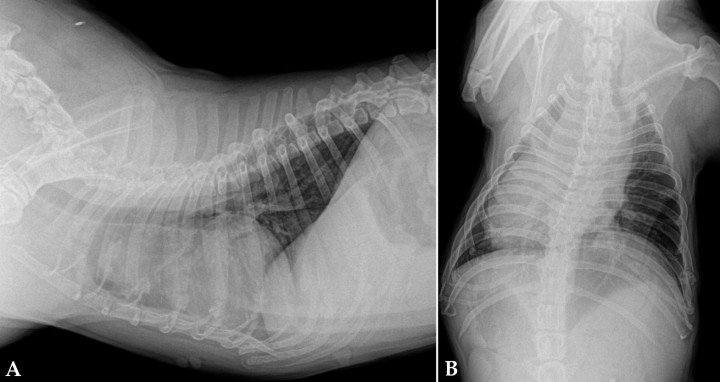

- Aumento de tamaño de la aurícula derecha (Fig. 3): produce un desplazamiento dorsal de la tráquea craneal a la carina sin afectar a esta en la proyección lateral.

<p>Radiografías de la cavidad torácica de un paciente con un tumor en la aurícula derecha. (<strong>A</strong>) Lateral. (<strong>B</strong>) Ventrodorsal.</p>

Radiografías de la cavidad torácica de un paciente con un tumor en la aurícula derecha. (A) Lateral. (B) Ventrodorsal.

- Aumento de tamaño del ventrículo derecho: en la proyección lateral se produce un aumento del contacto esternal debido a que el ventrículo derecho suele crecer en anchura. En la vista ventrodorsal se produce una imagen de “D invertida”.

- Derrame pericárdico (Fig. 4): produce una imagen globosa del corazón con desplazamiento dorsal de la tráquea e hipoperfusión pulmonar.

<p>Radiografías de la cavidad torácica de un paciente con derrame pericárdico. (<strong>A</strong>) Lateral. (<strong>B</strong>) Ventrodorsal.</p>

Radiografías de la cavidad torácica de un paciente con derrame pericárdico. (A) Lateral. (B) Ventrodorsal.

- Aumento de tamaño de base cardiaca (Fig. 5): se observa un desplazamiento dorsal de tráquea y aumento de tamaño en la proyección dorsoventral.

<p>Radiografías de la cavidad torácica de un paciente con tumor de base cardiaca. (<strong>A</strong>) Lateral. (<strong>B</strong>) Ventrodorsal.</p>

Radiografías de la cavidad torácica de un paciente con tumor de base cardiaca. (A) Lateral. (B) Ventrodorsal.